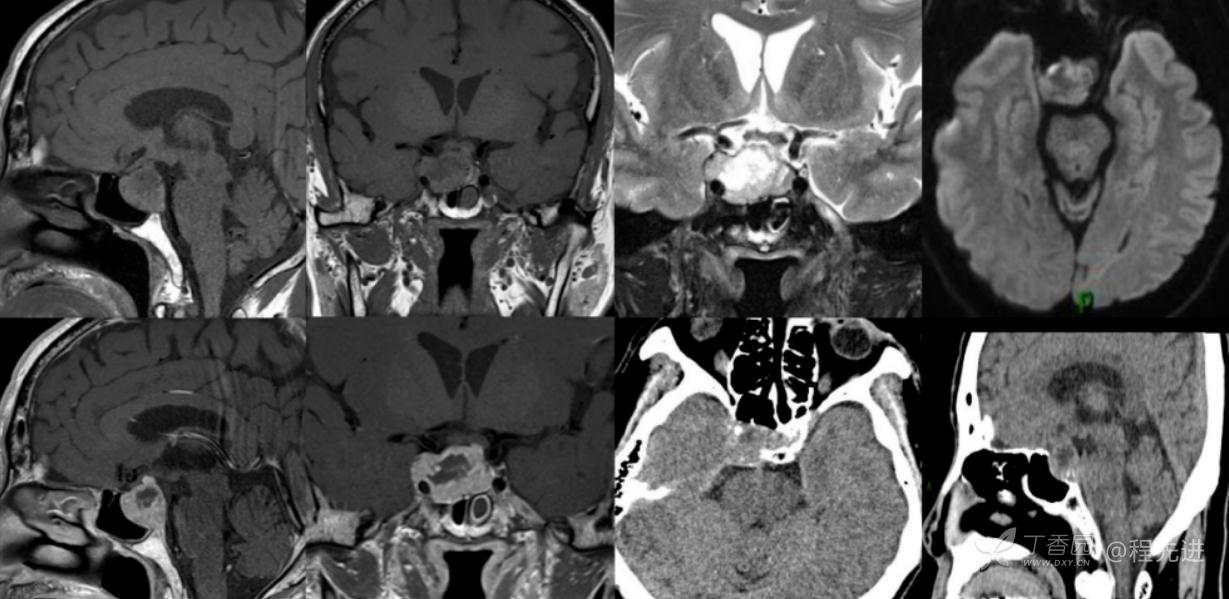

CT:

MR:

DWI及ADC图

T1+C

组合